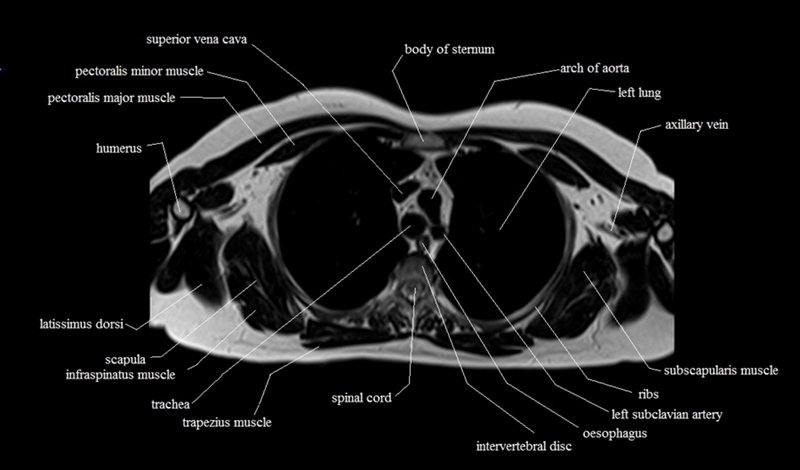

MRI Axial Cross Sectional Anatomy of Chest

This MRI chest (thorax) axial cross sectional anatomy tool is absolutely free to use. Use the mouse scroll wheel to move the images up and down, or alternatively, use the tiny arrows (→) on both sides of the image to navigate through the images. For a more detailed view, double-click the image to view it in full screen, and use the menu in the top right-hand corner to view individual slides or play them in a loop.